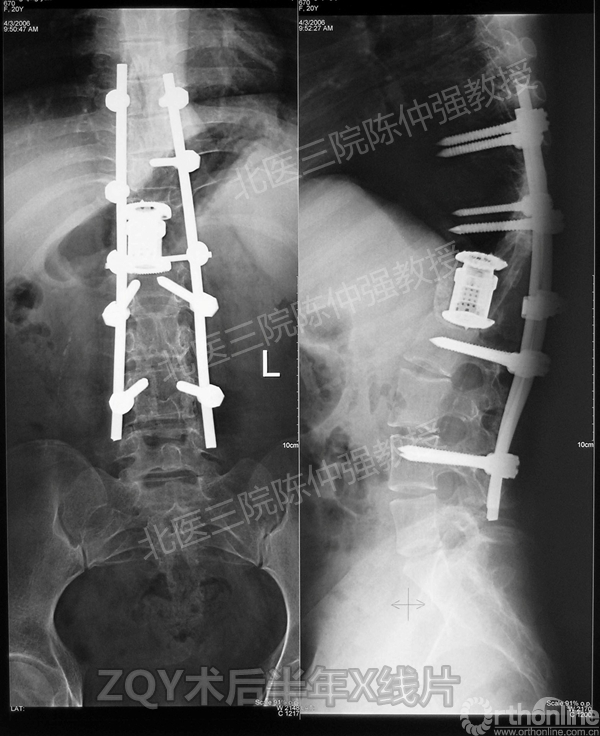

ZQY术后半年

患者女性17岁,胸腰椎陈旧结核性侧后凸畸形,局部呈“麻花状”扭转,无神经功能受损表现。2005年,陈仲强教授带领团队实施后路+侧前方联合入路脊柱节段切除、双轴旋转矫形术。术后患者外观显著改善,神经功能正常。术后随访证实患者截骨矫形节段骨性融合良好,矫形效果持续良好。